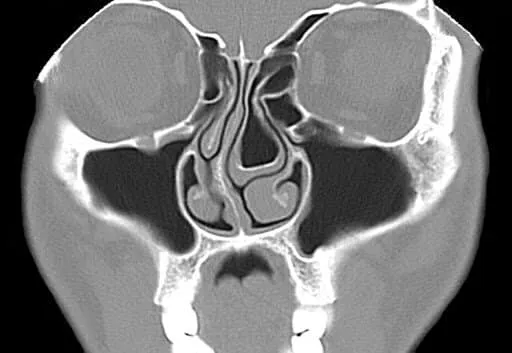

En ocasiones, se solicitan imágenes avanzadas, como una tomografía computarizada, si se sospecha que hay complicaciones, por ejemplo, si la infección se disemina más allá de los senos paranasales. Sin embargo, estas pruebas son poco frecuentes y se reservan para casos complejos.